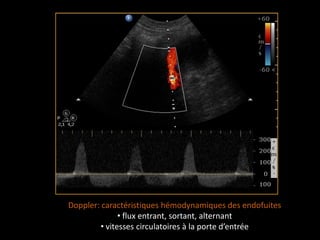

Doppler: caractéristiques hémodynamiques des endofuites

• flux entrant, sortant, alternant

• vitesses circulatoires à la porte d’entrée

Doppler: caractéristiques hémodynamiquesdes endofuites • flux entrant, sortant, alternant • vitesses circulatoires à la porte d’entrée